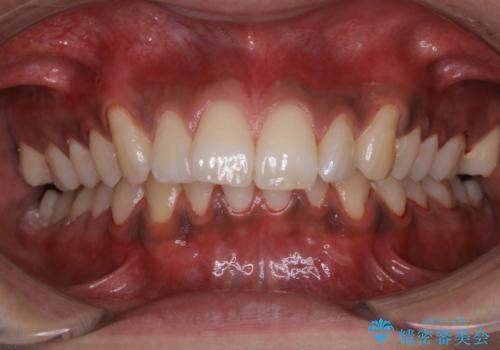

歯についたタバコのヤニをPMTCで綺麗に

- 電子タバコを吸う習慣があり、ステインがついてしまっている見た目が気になるとのことで来院されました。ステインだけではなく、歯石も全体的に付着していたためPMTC60分コースを行いました。